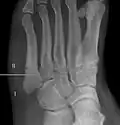

![]() | |

| Jones fracture as seen on Xray | |

Diagnostic X-rays include anteroposterior, oblique, and lateral views and should be made with the foot in full flexion.